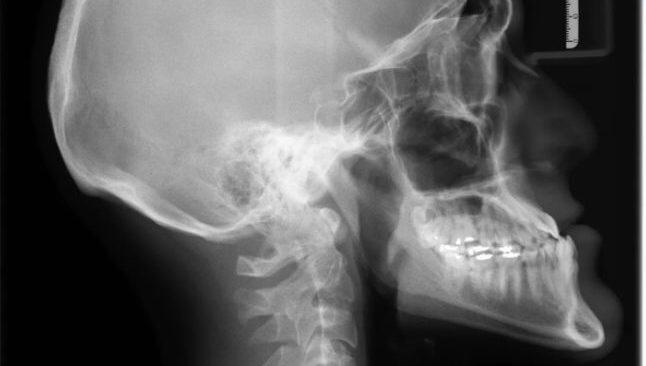

Clavó no llegó al cerebro

De acuerdo con las radiografías, el clavo fue clavado cinco centímetros en el cráneo y no logró llegar al cerebro. https://t.me/QAnons_Espana